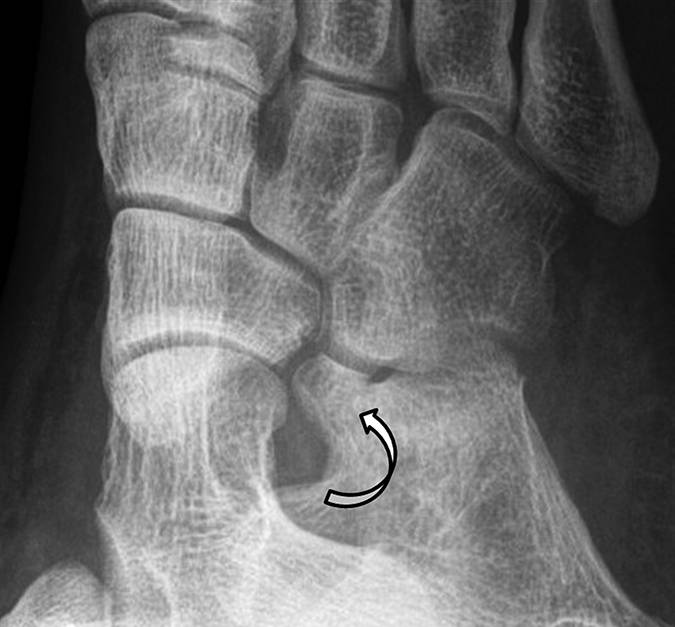

图4A-男,43岁,从马身上掉下来,经历过疼痛,踝关节背部出现瘀伤。A,在损伤后2天获得的X线照片显示了在关节上方约5cm处的跟腱中的骨片(箭头)。

图4B-男,43岁,从马身上掉下来,经历过疼痛,踝关节背部出现瘀伤。B,损伤后6周获得的矢状T1加权MR图像显示加厚的跟腱。 在腱内存在不均匀的信号强度,低信号强度的区域(直箭头)在撕脱位置上方约5cm处, 结节撕脱缺损(弯曲的箭头)